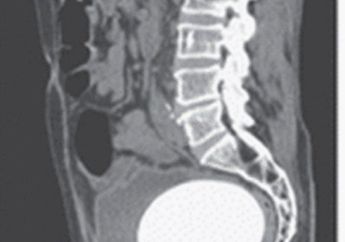

Busett! Batu Sebesar Telur Burung Unta 'Nyangkut' Di Saluran Kandung Kemih Seorang Pria

8 Tahun yang lalu - Pria itu hingga kesakitan karena tidak bisa kencing.